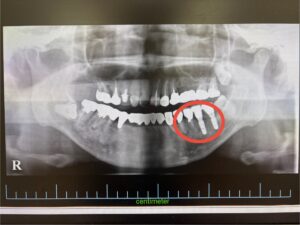

レントゲン検査を行ったところ、左下奥歯2本の歯根破折が確認されました。

術前